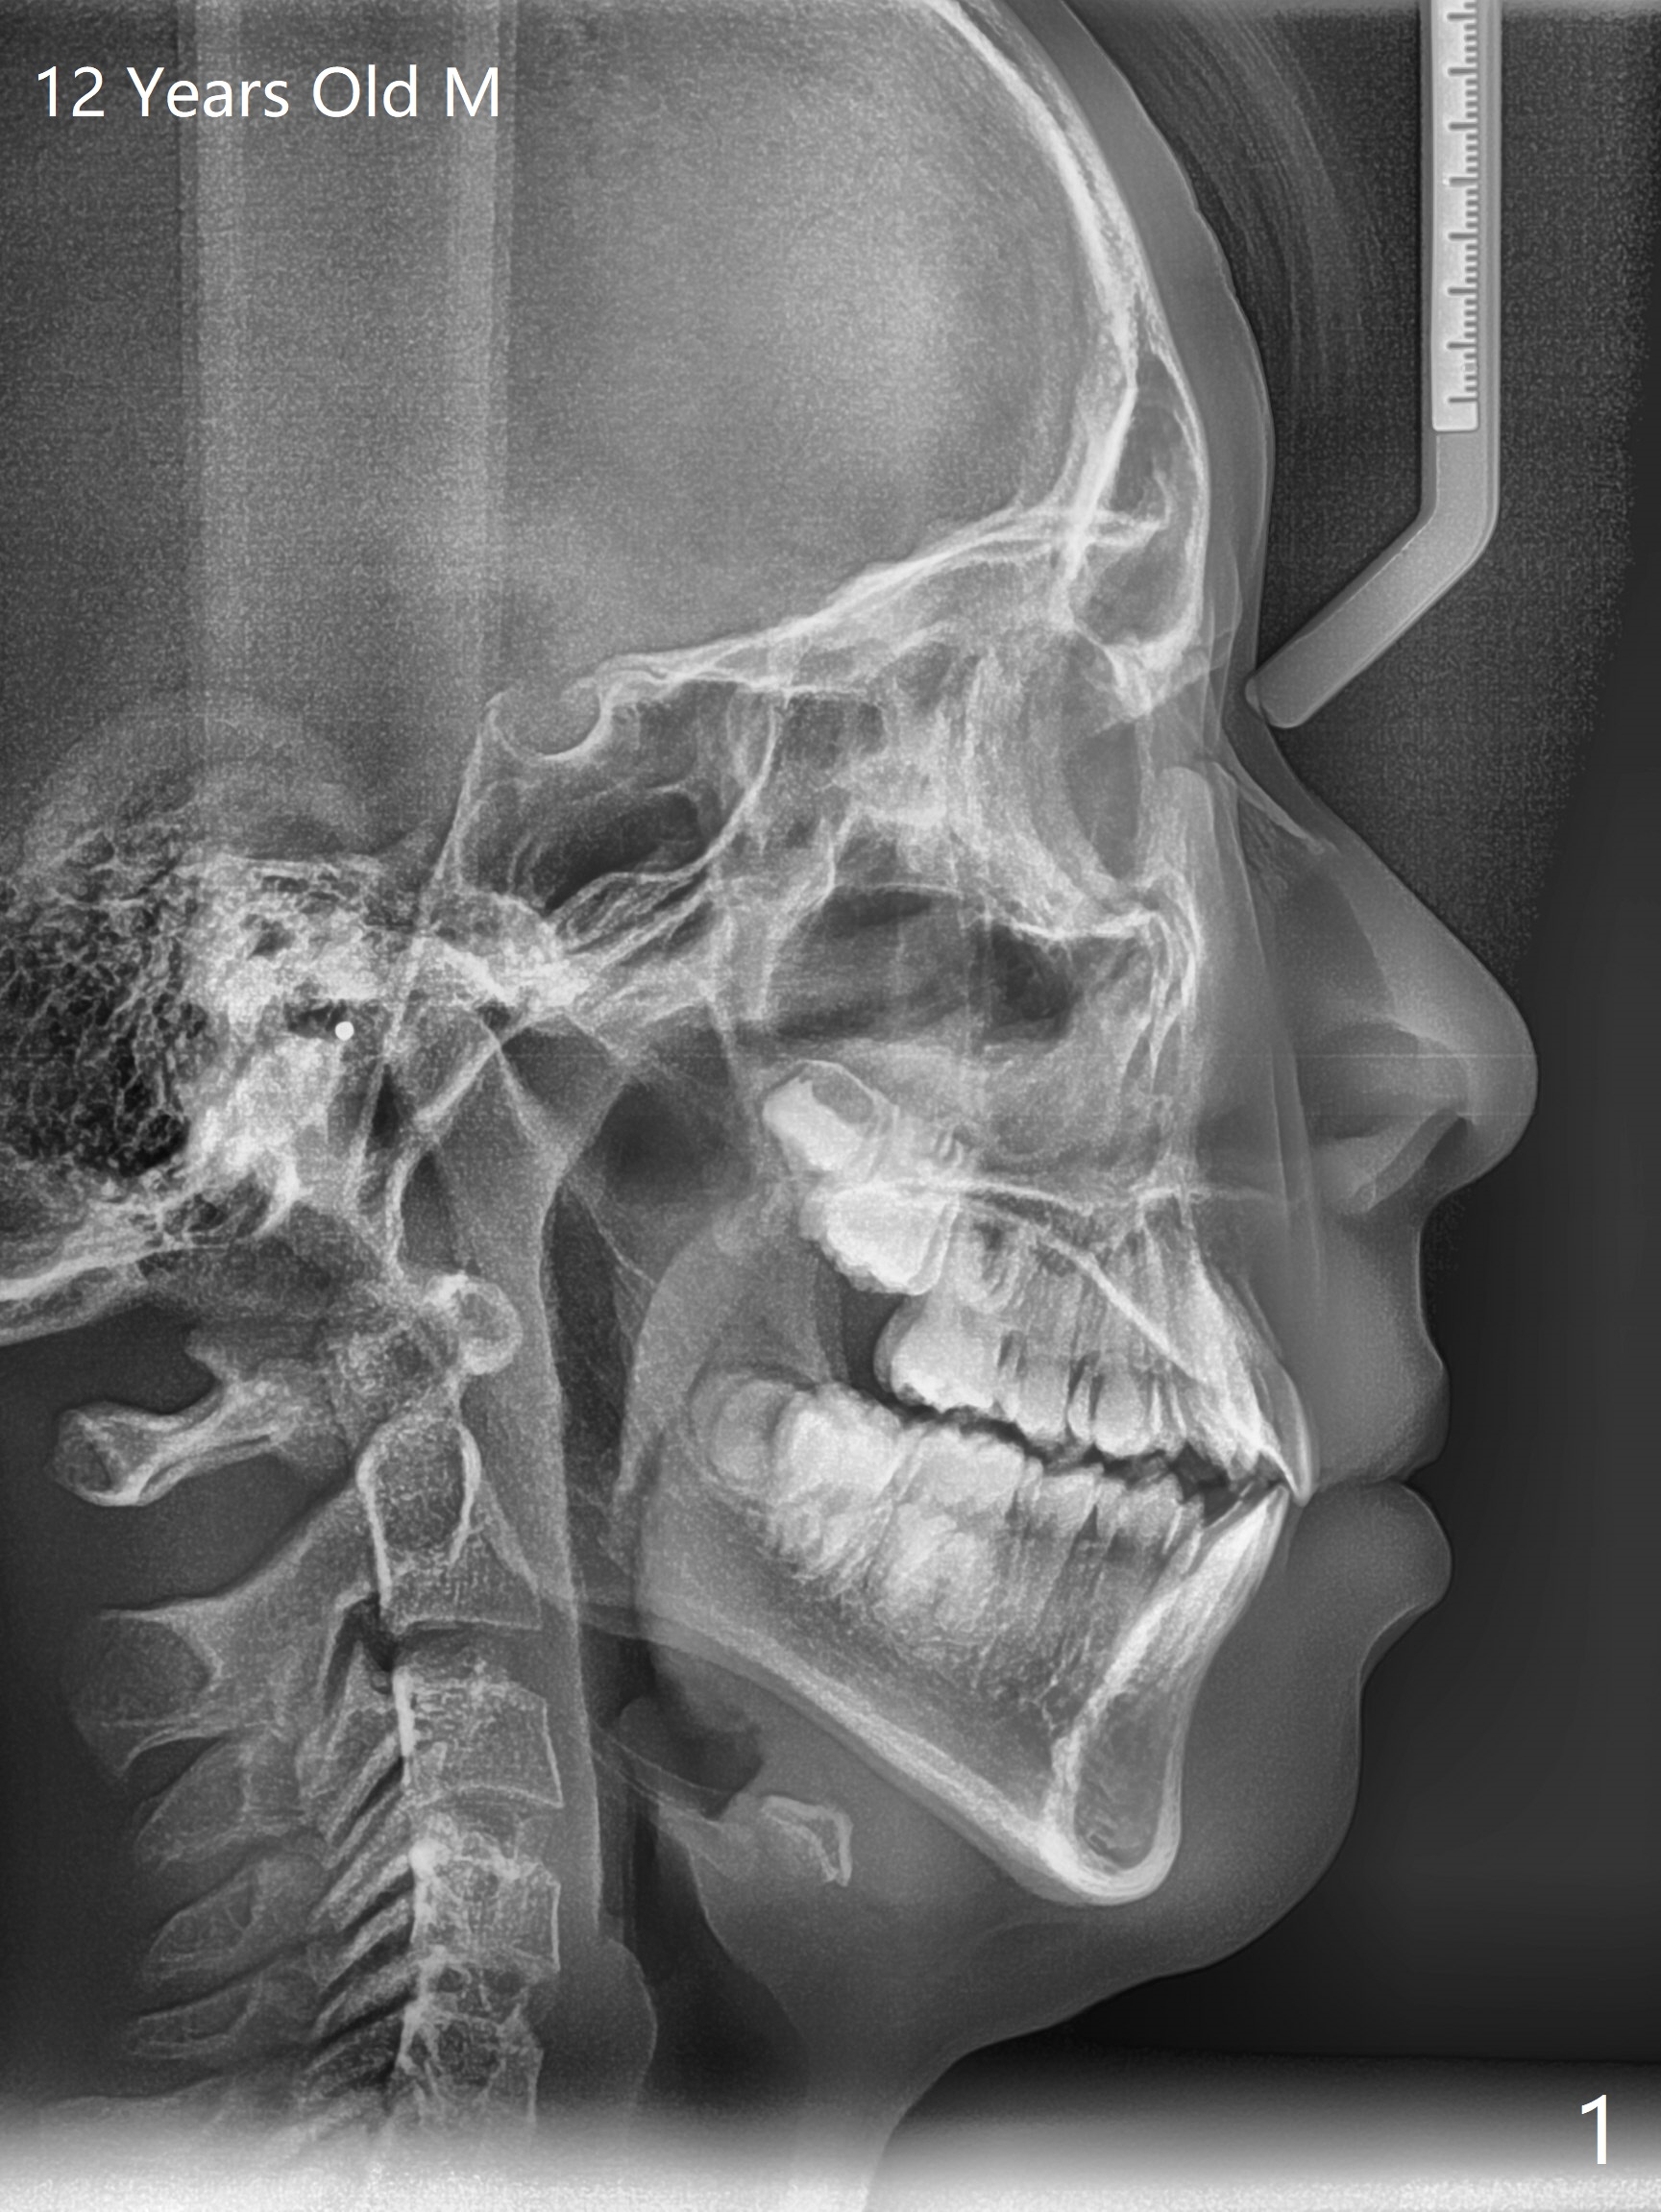

Shallow Overbite

A 12-year-old man has mild lip protrusion (Fig.1,6,7). Orthodontics will be conducted without extraction. Unlike his elder brother, the overbite is shallow. With anterior bracket differential (4-4-5 mm) and mild bimaxillary protrusion, open bite will be created? Or 4-4-4.5mm scheme should be adopted to avoid open bite?